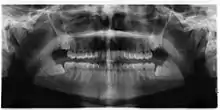

Panoramic radiograph of impacted lower wisdom teeth (green arrows) in a 26-year-old with dental caries (red arrows) on the adjacent teeth

The diagnosis of impaction can be made clinically if enough of the wisdom tooth is visible to determine its angulation, depth, and if the patient is old enough that further eruption or uprighting is unlikely. Wisdom teeth continue to move to the age of 25 years old due to eruption, and then continue some later movement owing to periodontal disease.[18]

If the tooth cannot be assessed with clinical exam alone, the diagnosis is made using either a panoramic radiograph or cone-beam CT. Where unerupted wisdom teeth still have eruption potential several predictors are used to determine the chance of the teeth becoming impacted. The ratio of space between the tooth crown length and the amount of space available, the angle of the teeth compared to the other teeth are the two most commonly used predictors, with the space ratio being the most accurate. Despite the capacity for movement into early adulthood, the likelihood that the tooth will become impacted can be predicted when the ratio of space available to the length of the crown of the tooth is under 1.[5]:141